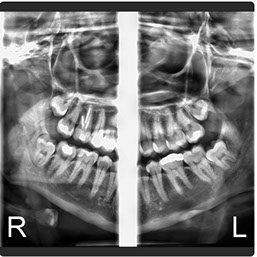

Radiografía Panorámica Digital

Radiografía Panorámica

El Eagle 2D Pan/Tele ofrece todos los exámenes en el perfil panorámico (panorámica estándar, senos maxilares, baja dosis, bitewing, ATM, ortogonalidad perfeccionada, panorámica infantil y bitewing ortogonalidad perfeccionada) y todos los exámenes en el perfil cefalométrico (Posteroanterior, Antero-posterior, 45 Grados, Lateral, Carpal, PA de Walters, Axial Bazal, Hirtz).

La línea Eagle ofrece alta calidad de imagen, facilidad de operación, fácil posicionamiento del paciente y reúne lo mejor de la tecnología mundial en todas las funciones. El generador de rayos X de alta frecuencia reduce la exposición innecesaria del paciente. El sistema de microprocesado de alta velocidad y la mecánica precisa permiten la perfecta ejecución y repetición en imágenes 2D y 3D